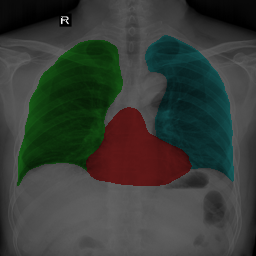

To bridge the methodological gaps when only small-scale partially labeled data is available, we propose a simple yet efficient framework Vicinal Labels Under Uncertainty (VLUU) by exploring the statistical similarity of human structures (e.g. shape, size, location) among different patients. See Fig. 1 for an illustration of such a similarity. The proposed framework is motivated by vicinal risk minimization (VRM) [11], where the fully labeled vicinal examples are generated by linearly combining randomly sampled partial labels with a weight randomly sampled from a Dirichlet distribution. These vicinal examples allow us to transform the partially supervised problem into a fully supervised one. That is to say, we can utilize any existing supervised segmentation networks and loss functions to solve partially supervised problems. The generated vicinal labels contain uncertainty regions where classes of interest could potentially overlap. We utilize these uncertainties in the training process to improve the robustness of DL models.

In standard adversarial training, the segmentation network and the discriminator play a zero-sum game. The discriminator is trained to discriminate the prediction masks produced by the segmentation network from the ground truth masks. Meanwhile, the segmentation network is trained to confuse the discriminator by producing realistic prediction masks. Adversarial training benefits from the human structure similarity as it makes the unknown true label distributions easier to be caught by the discriminator than for general objects [38]. In other words, there is smaller instance-wise variation in the size, shape, and location of human organs (or structures), as shown in Fig. 1, than for general objects.